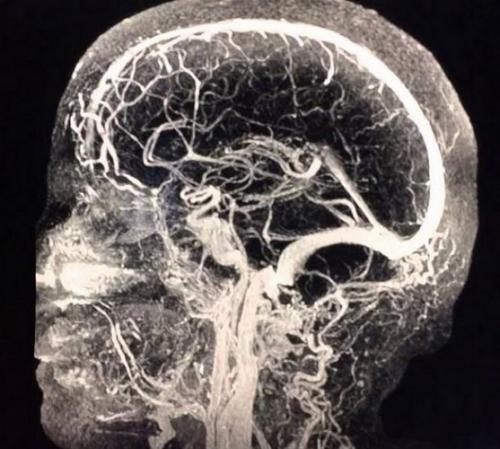

МРТ ангиография сосудов головного мозга (сагиттальный срез)

В диагностике поражений сосудов головного мозга МРТ с использованием режима МР-ангиографии визуализирует малейшие изменения в работе кровеносной системы.

Процедура позволяет диагностировать:

- стенозы, окклюзии - сужение и закупорку сосудистого русла;

- острое нарушение кровообращения в тканях;

- аневризму - выпячивание артериальной стенки;

- тромбозы - образование сгустка в просвете вены;

- разрывы сосудистой стенки;

- атеросклероз - отложения холестерина в просвете артерии;

- васкулиты - воспалительные изменения, утолщение и расслоение стенок;

- эмболии - перекрывание просвета артерии инородными частицами (газовой, паразитарной и др. природы);

- синдром экстравазальной компрессии - внешнее сдавление сосудистого русла;

- артерио-венозные мальформации - патологические анастомозы (соединения) кровеносных каналов;

- врожденные аномалии сосудистой системы - перегибы, раздвоения и пр;

- диссекцию (расслоение) аорты;

- тромбофлебиты - воспаление стенок вен с образованием кровянистых сгустков;

- сосудистые опухоли.